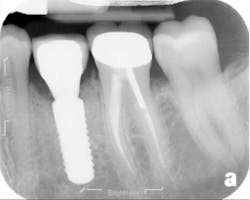

The patient was seen four months later for Stage II uncovering of her implant using a tissue punch and was sent to her restorative dentist for final impressions two weeks after that. Three months after the initial surgery, the patient returned with her final restoration in place for a soft-tissue exam and radiograph. Six months after surgery, she returned for a postdelivery radiograph, shown here. (I see every implant patient three months after seating the final restoration to check for residual cement, ensure that the restorative apparatus is fully seated, and check the soft- and hard-tissue response to the new restoration. This is an extremely important—and often overlooked visit—where problems are often noted that can cause significant damage to the bone and gingiva if early intervention is not initiated.) The bone levels were well-maintained around the implant platform, and the soft-tissue health was excellent. The patient reported a high degree of satisfaction with her new implant restoration.